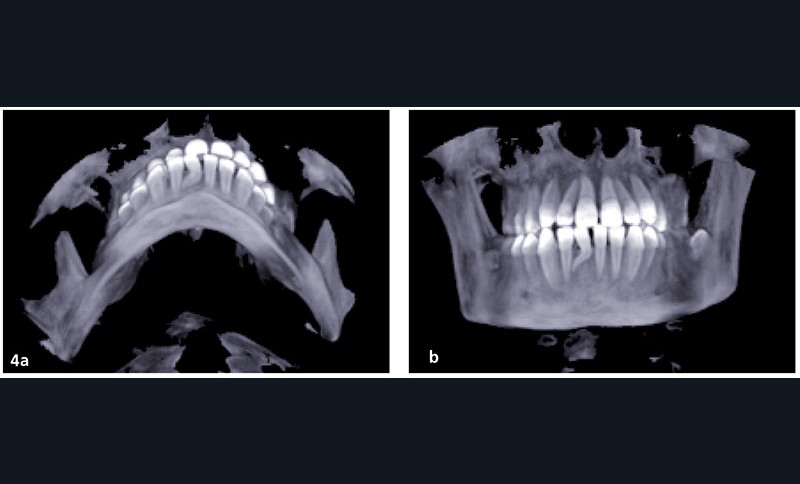

L’objectif est de rééquilibrer l’occlusion dentaire en réalisant des compensations dento-alvéolaires sans modifier le squelette. La chirurgie maxillo-faciale est écartée (fig. 3 et 4).